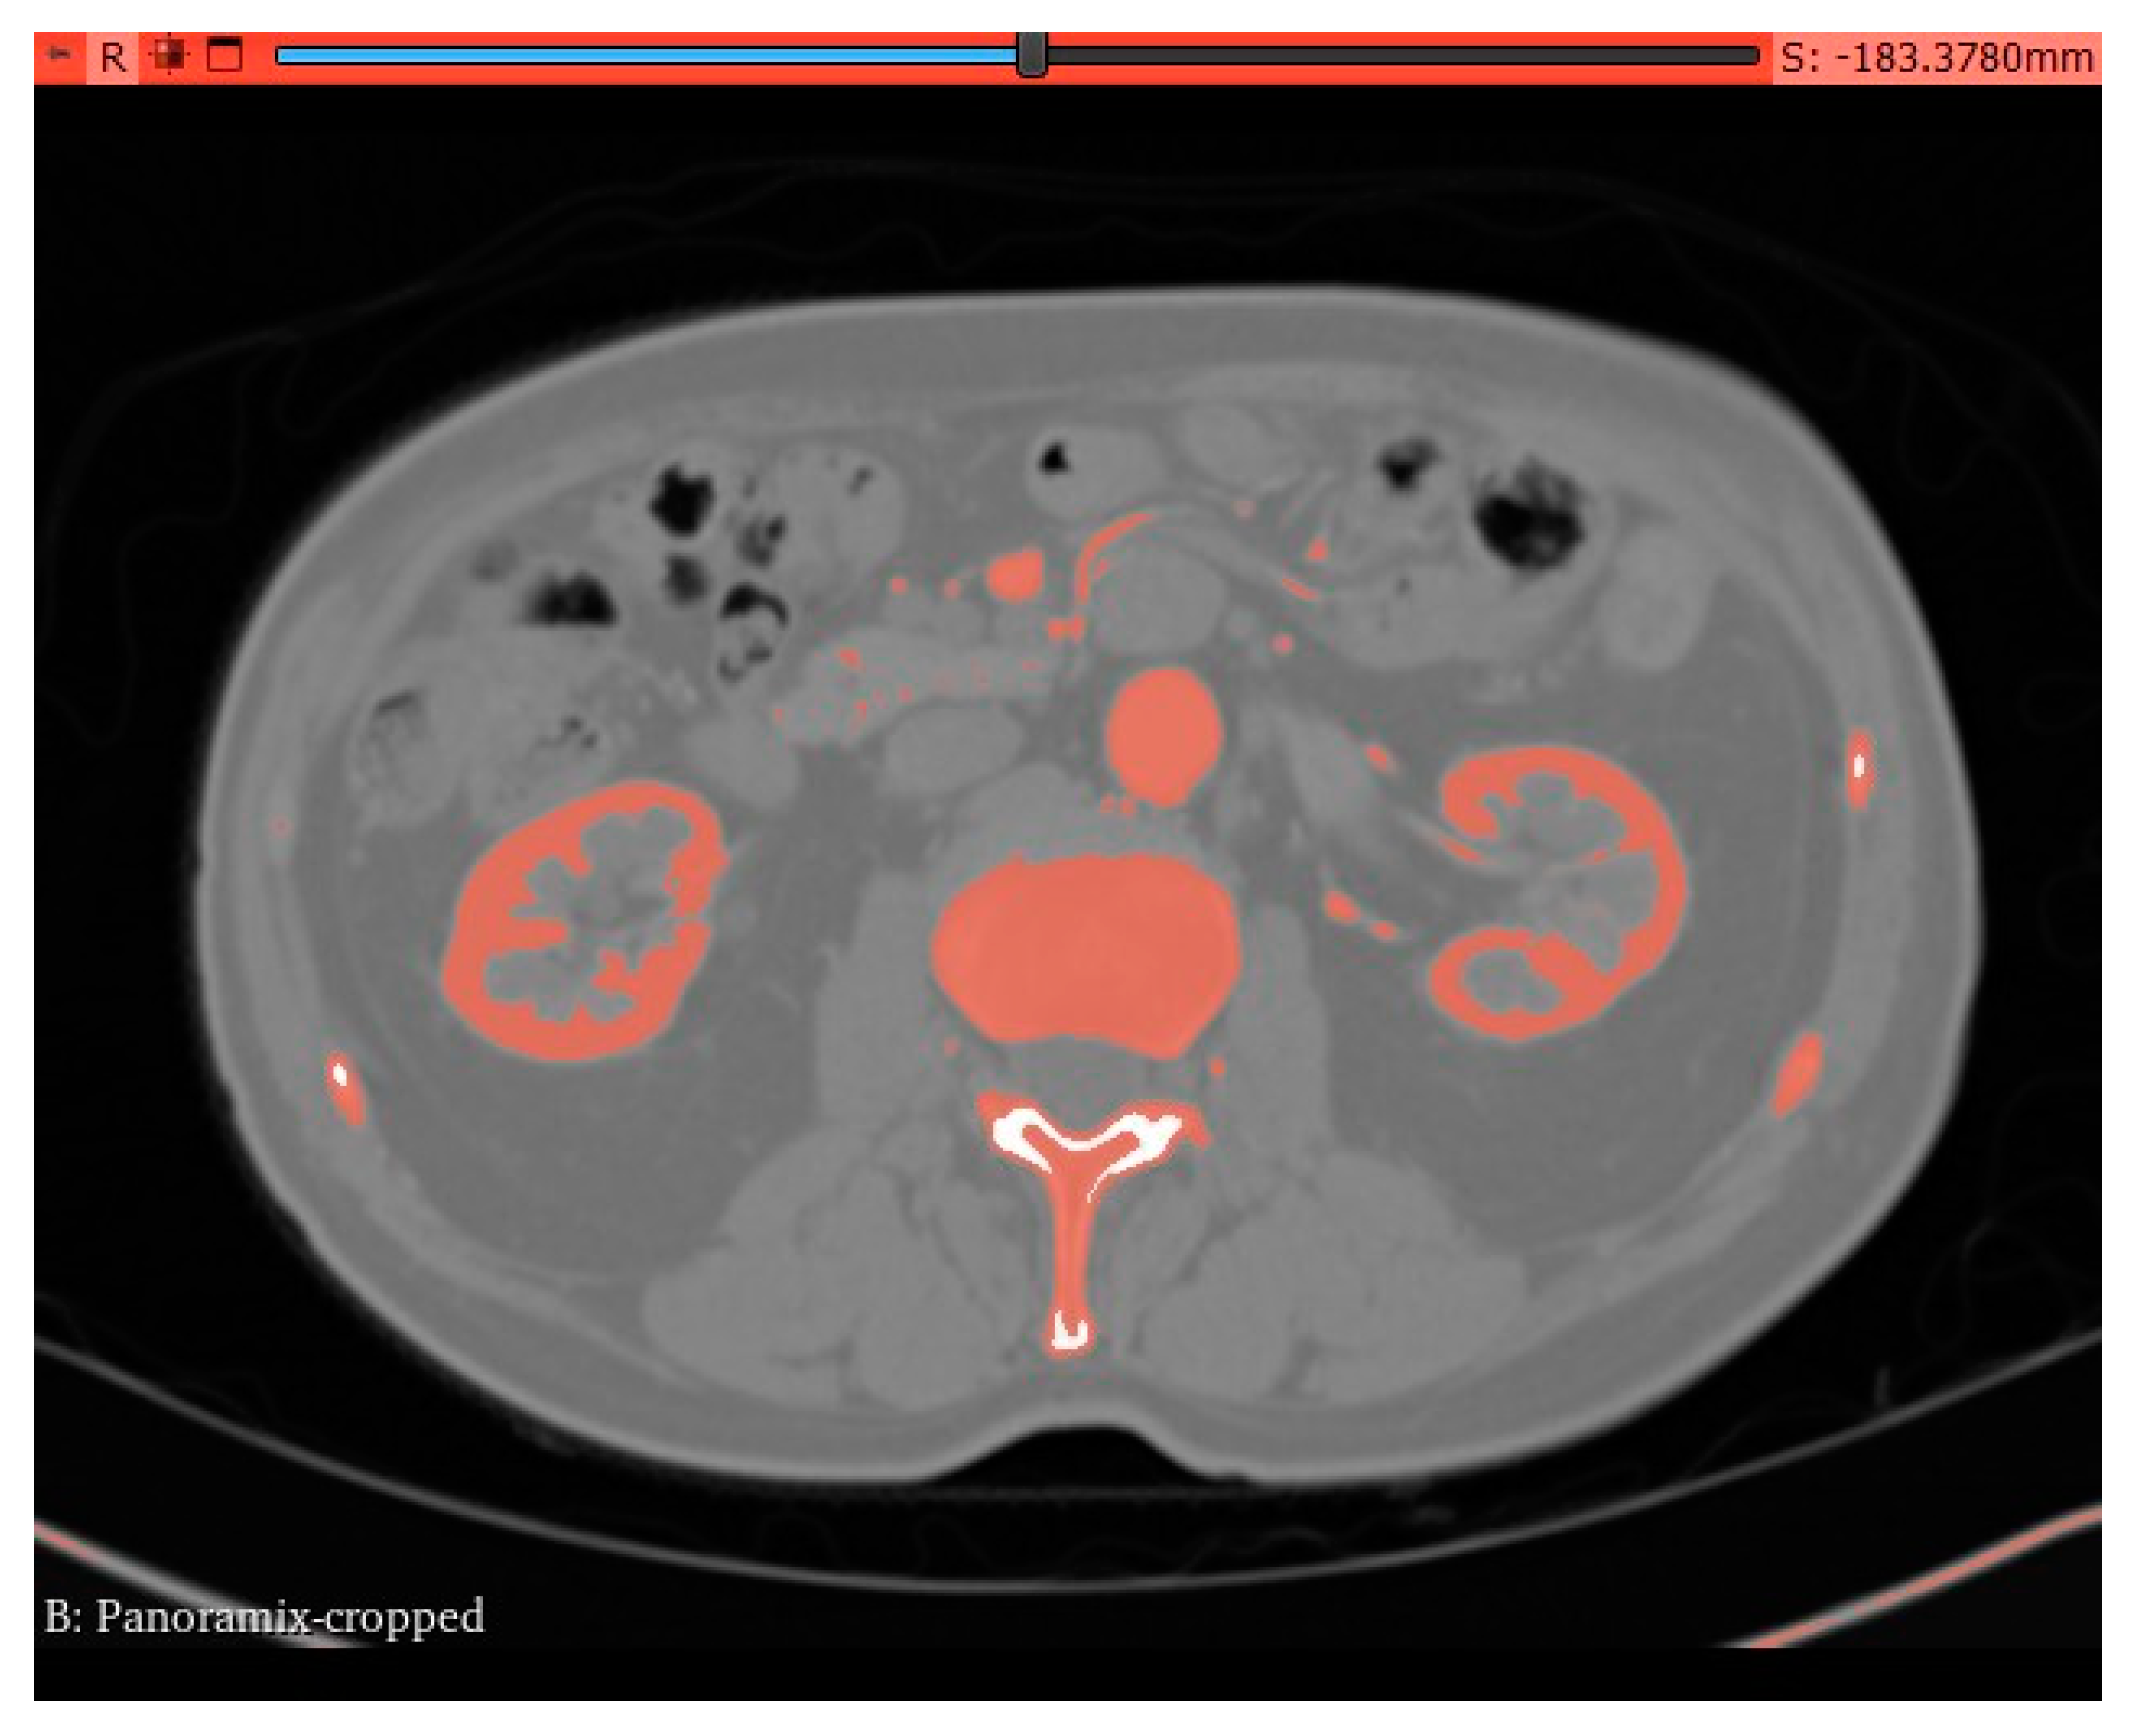

Utilizing computed tomography (CT) abdomen scans procured from online repositories such as 3D Embodi and the NHIA database in NRRD file format with saggital, axial and coronal view of abdomen CT. A meticulous 1-1 reconstruction of the abdominal cavity of patients was meticulously orchestrated employing the open-source software known as 3D Slicer—an advanced tool designed for scientific data visualization. The CT scans were seamlessly imported into 3D Slicer, where a distinctive segment dedicated to the abdomi- nal aorta was meticulously delineated within the ”segmentations” module. The following figure depicts the abdominal aortic segments in axial and sagittal CT scans.

Figure 2. Axial Segmentation.

Preprints 96905 g002

Figure 5. Source volume - panaromix cropped.

Preprints 96905 g005